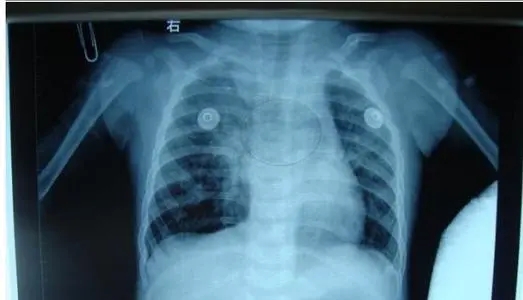

縱隔疝的診斷主要依賴胸部X線檢查,后前位胸片和縱隔肺門常規(guī)斷層片可見局部透亮區(qū)域超過氣管軸線,是肺組織疝入對側(cè)胸腔的征象,疝入對側(cè)的肺組織內(nèi)很少 見肺紋理,胸部CT可以清晰地顯示縱隔疝的部位和范圍,對于確診價(jià)值很大,此外,胸部X線檢查多有助于明確導(dǎo)致縱隔疝的原發(fā)疾病的診斷。